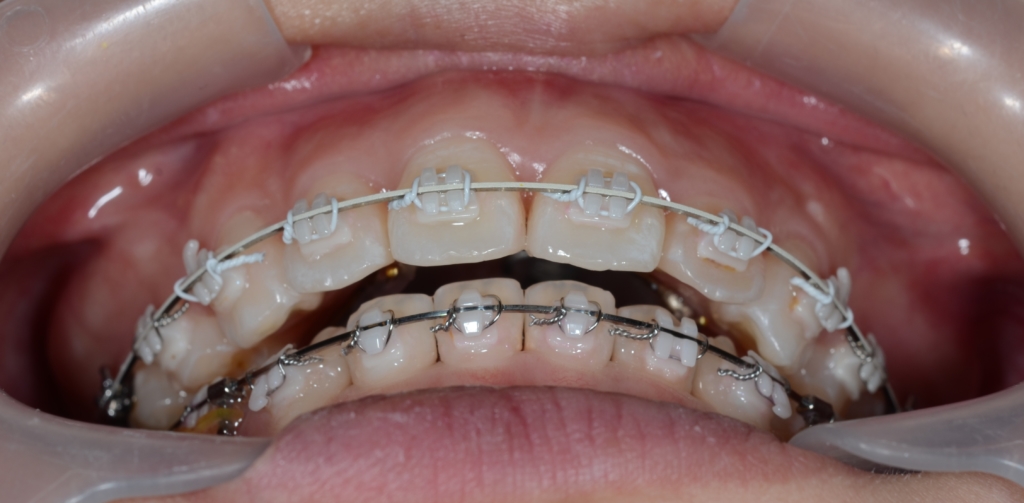

最後に、矯正治療前後の「歯並び」、「レントゲン写真」と「横顔と口元の写真」の比較をお見せしましょう。

先ずは。歯並びの比較から。